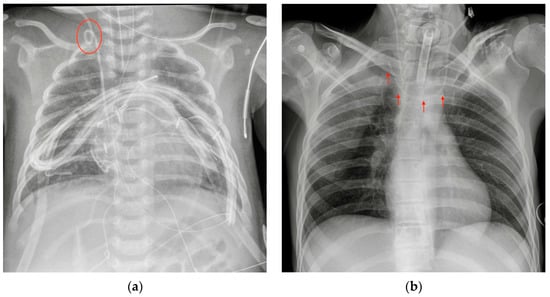

8.1. Cerebrospinal Fluid (CSF) Shunts

8.2. Vagal Nerve Stimulator (VNS)